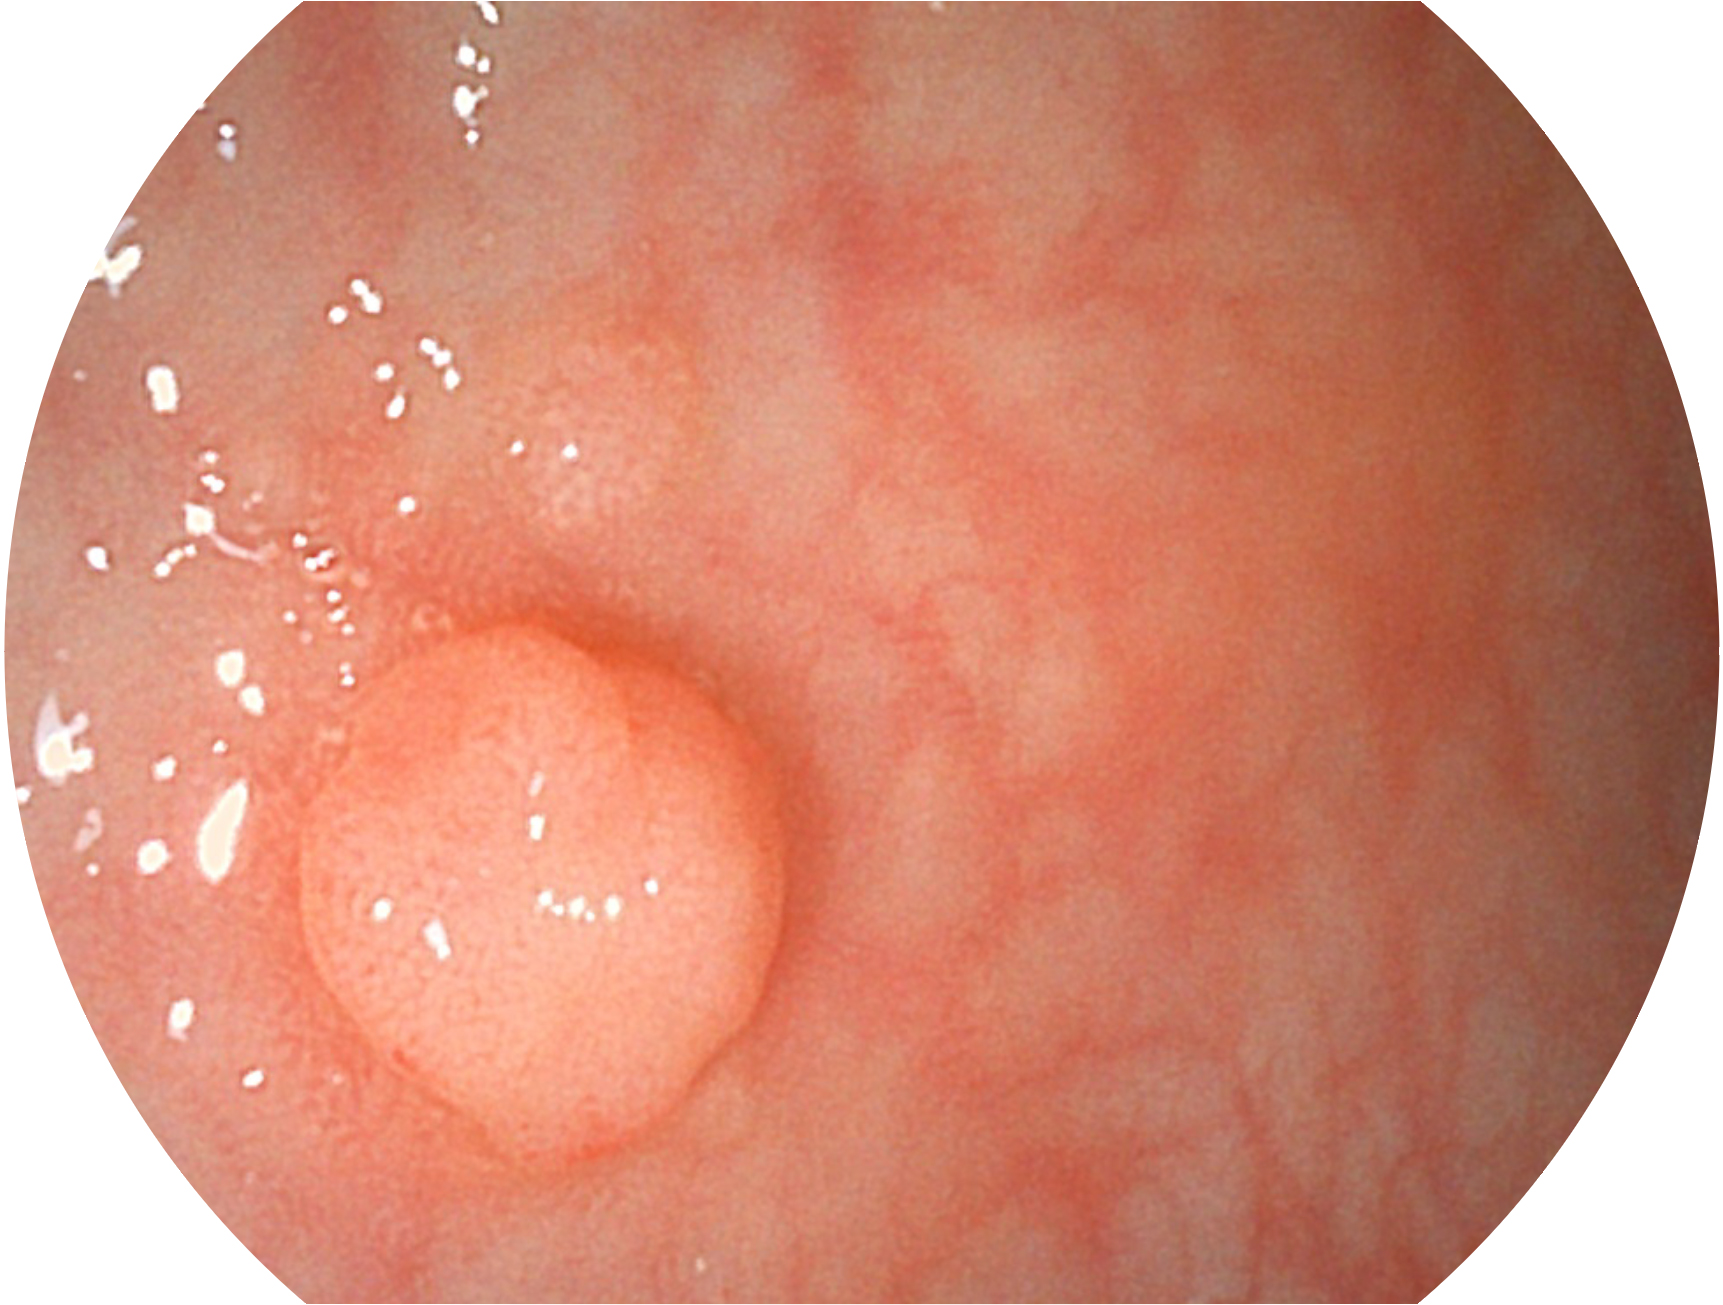

银河集团官网新开发的内镜染色技术,主要是基于多波长LED 光源的开发,VLS-55Q 四波长LED 光源是由四个不同颜色的LED光按照相应照明模式所规定的特定发光比例进行合束后形成,合束后形成的照明光的光谱由红光、绿光、蓝光及蓝紫光这四个不同的波段范围构成。具有更高光谱自由度,通过光谱比例的控制,实现了聚谱成像技术,英文全称为“Spectral Focused Imaging, SFI”,缩写为“SFI”和光电复合染色成像技术,英文全称为“Versatile Intelligent Staining Technology, VIST”,缩写为“VIST”。